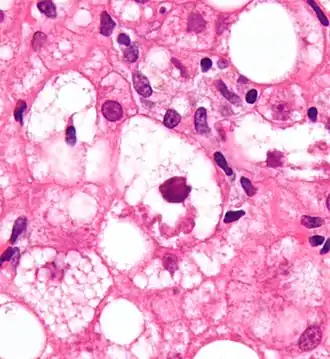

Mallory bodies are highly eosinophilic and thus appear pink on H&E stain. The bodies themselves are made up of intermediate cytokeratin 8/18 filament proteins that have been ubiquitinated, or bound by other proteins such as heat shock proteins, or p62/Sequestosome 1.[5]